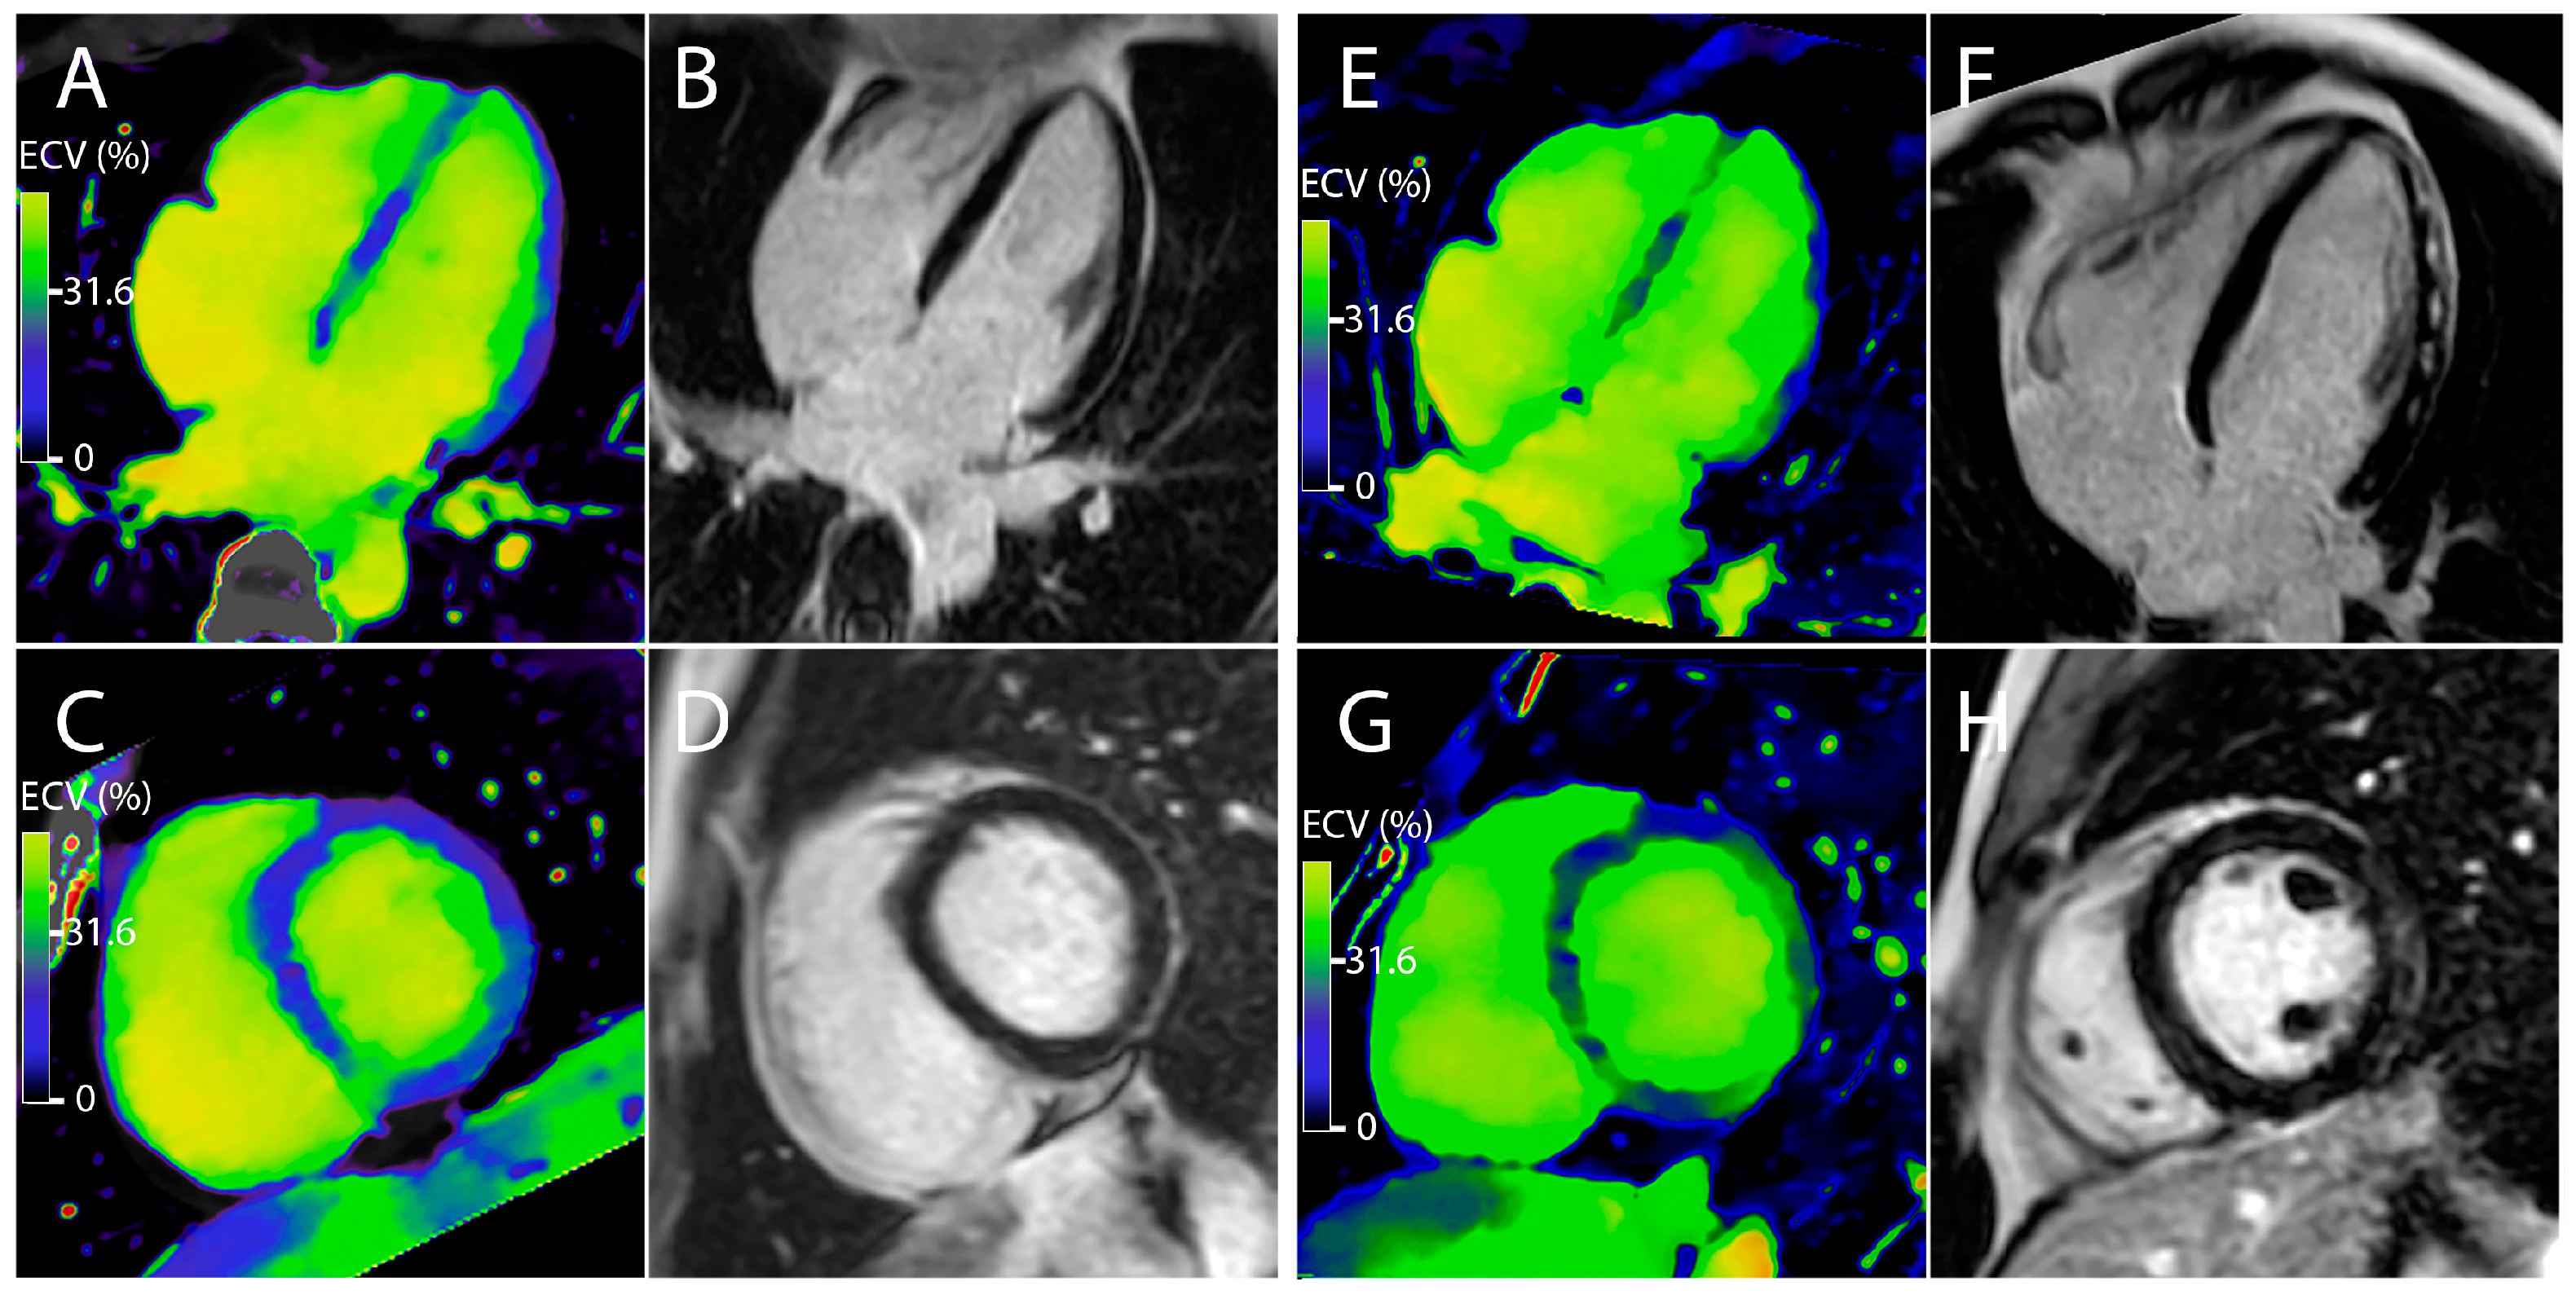

2.4.4. Image Analysis

3.2. Measurement of the Myocardial Inflammation

3.3. Correlation between ECV and the Different Parameters